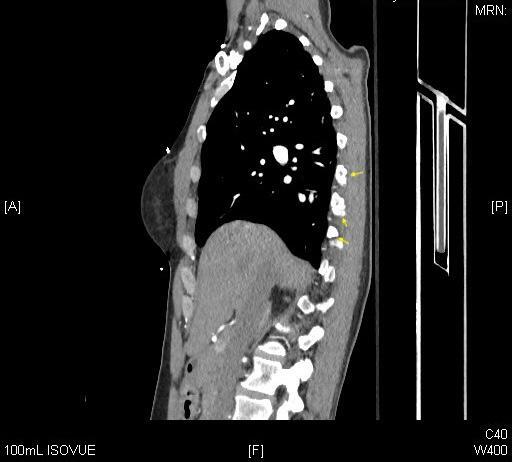

The CT scans of the abdomen and pelvis found no solid organ or hollow viscus injury. Spine CTs were negative for fracture or subluxation of the cervical, thoracic, or lumbar spine. Noncontrast brain CT was also negative for acute pathology. However, CT scans of the chest found right posterolateral third, fourth, fifth, sixth, seventh, eighth rib fractures [Figures 2,3]. A clavicle fracture was also found.